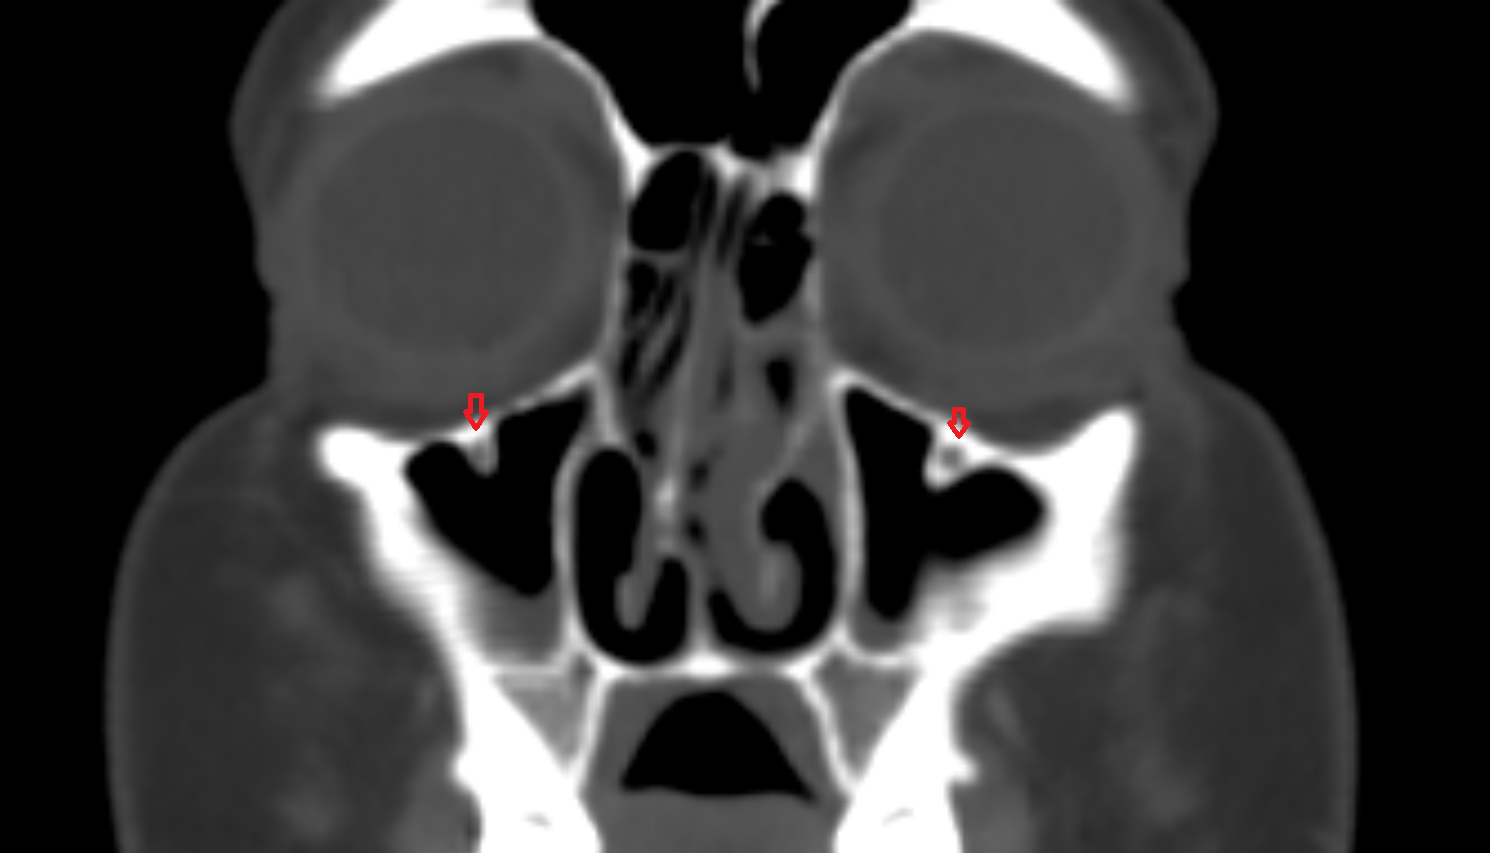

- Maxillary sinus